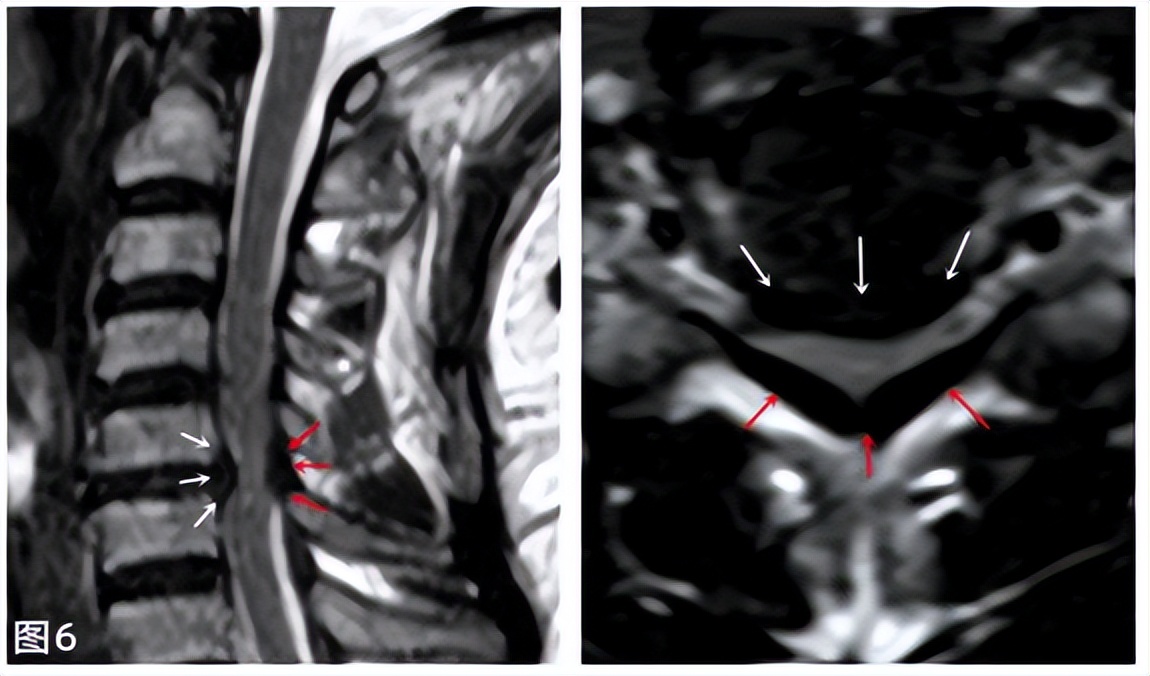

脊髓型颈椎病大多是由于椎间盘突出、韧带肥厚、骨质增生等多因素造成椎管狭窄(见图6,白色箭头系突出的间盘,红色箭头系肥厚的韧带),从而出现其内容纳的脊髓受压,开始可能并无症状,因脊髓有一定的耐受能力,后期达到最大耐受限度或者说突然外力影响下,脊髓就会出现损伤,导致其支配平面以下广泛的感觉运动功能障碍,比如 双上肢双手麻木无力、双手笨拙、胸腹部发紧感、行走不稳有踩棉花感、大小便费力等等 。